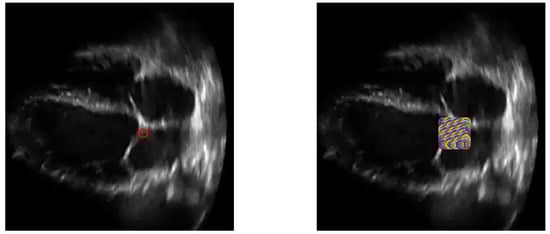

1. Introduction

2.3. Creating Prongs

2.4. Estimating Movement of Mitral Valve